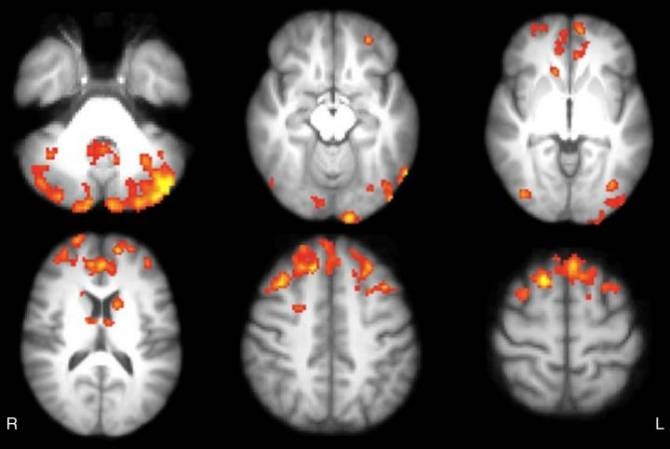

Diferencia en la conectividad funcional talámica entre pacientes con esclerosis múltiple y sujetos sanos. (Imágenes: Radiological Society of North America)

Tras el seguimiento, los 12 pacientes en el grupo de los videojuegos mostraron aumentos notables en la conectividad funcional talámica, en áreas cerebrales que se corresponden con el componente posterior de la red neuronal por defecto, que es una de las más importantes implicadas en la cognición.